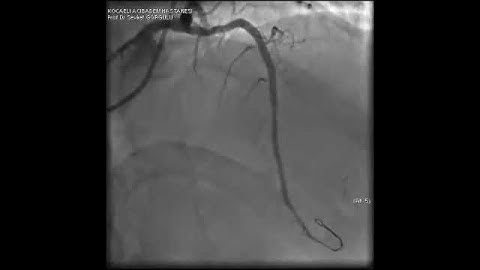

Microcatheter Tip Fracture During LAD CTO PCI: A Complication Video 3